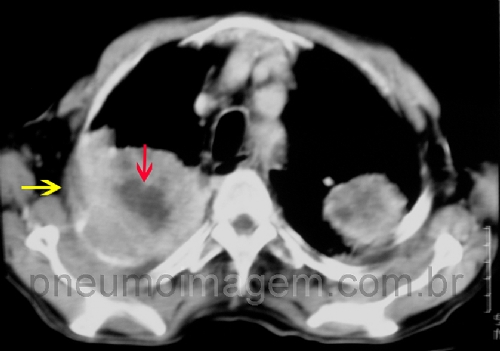

Veja imagens de câncer de pulmão no PneumoImagem, clique aqui.